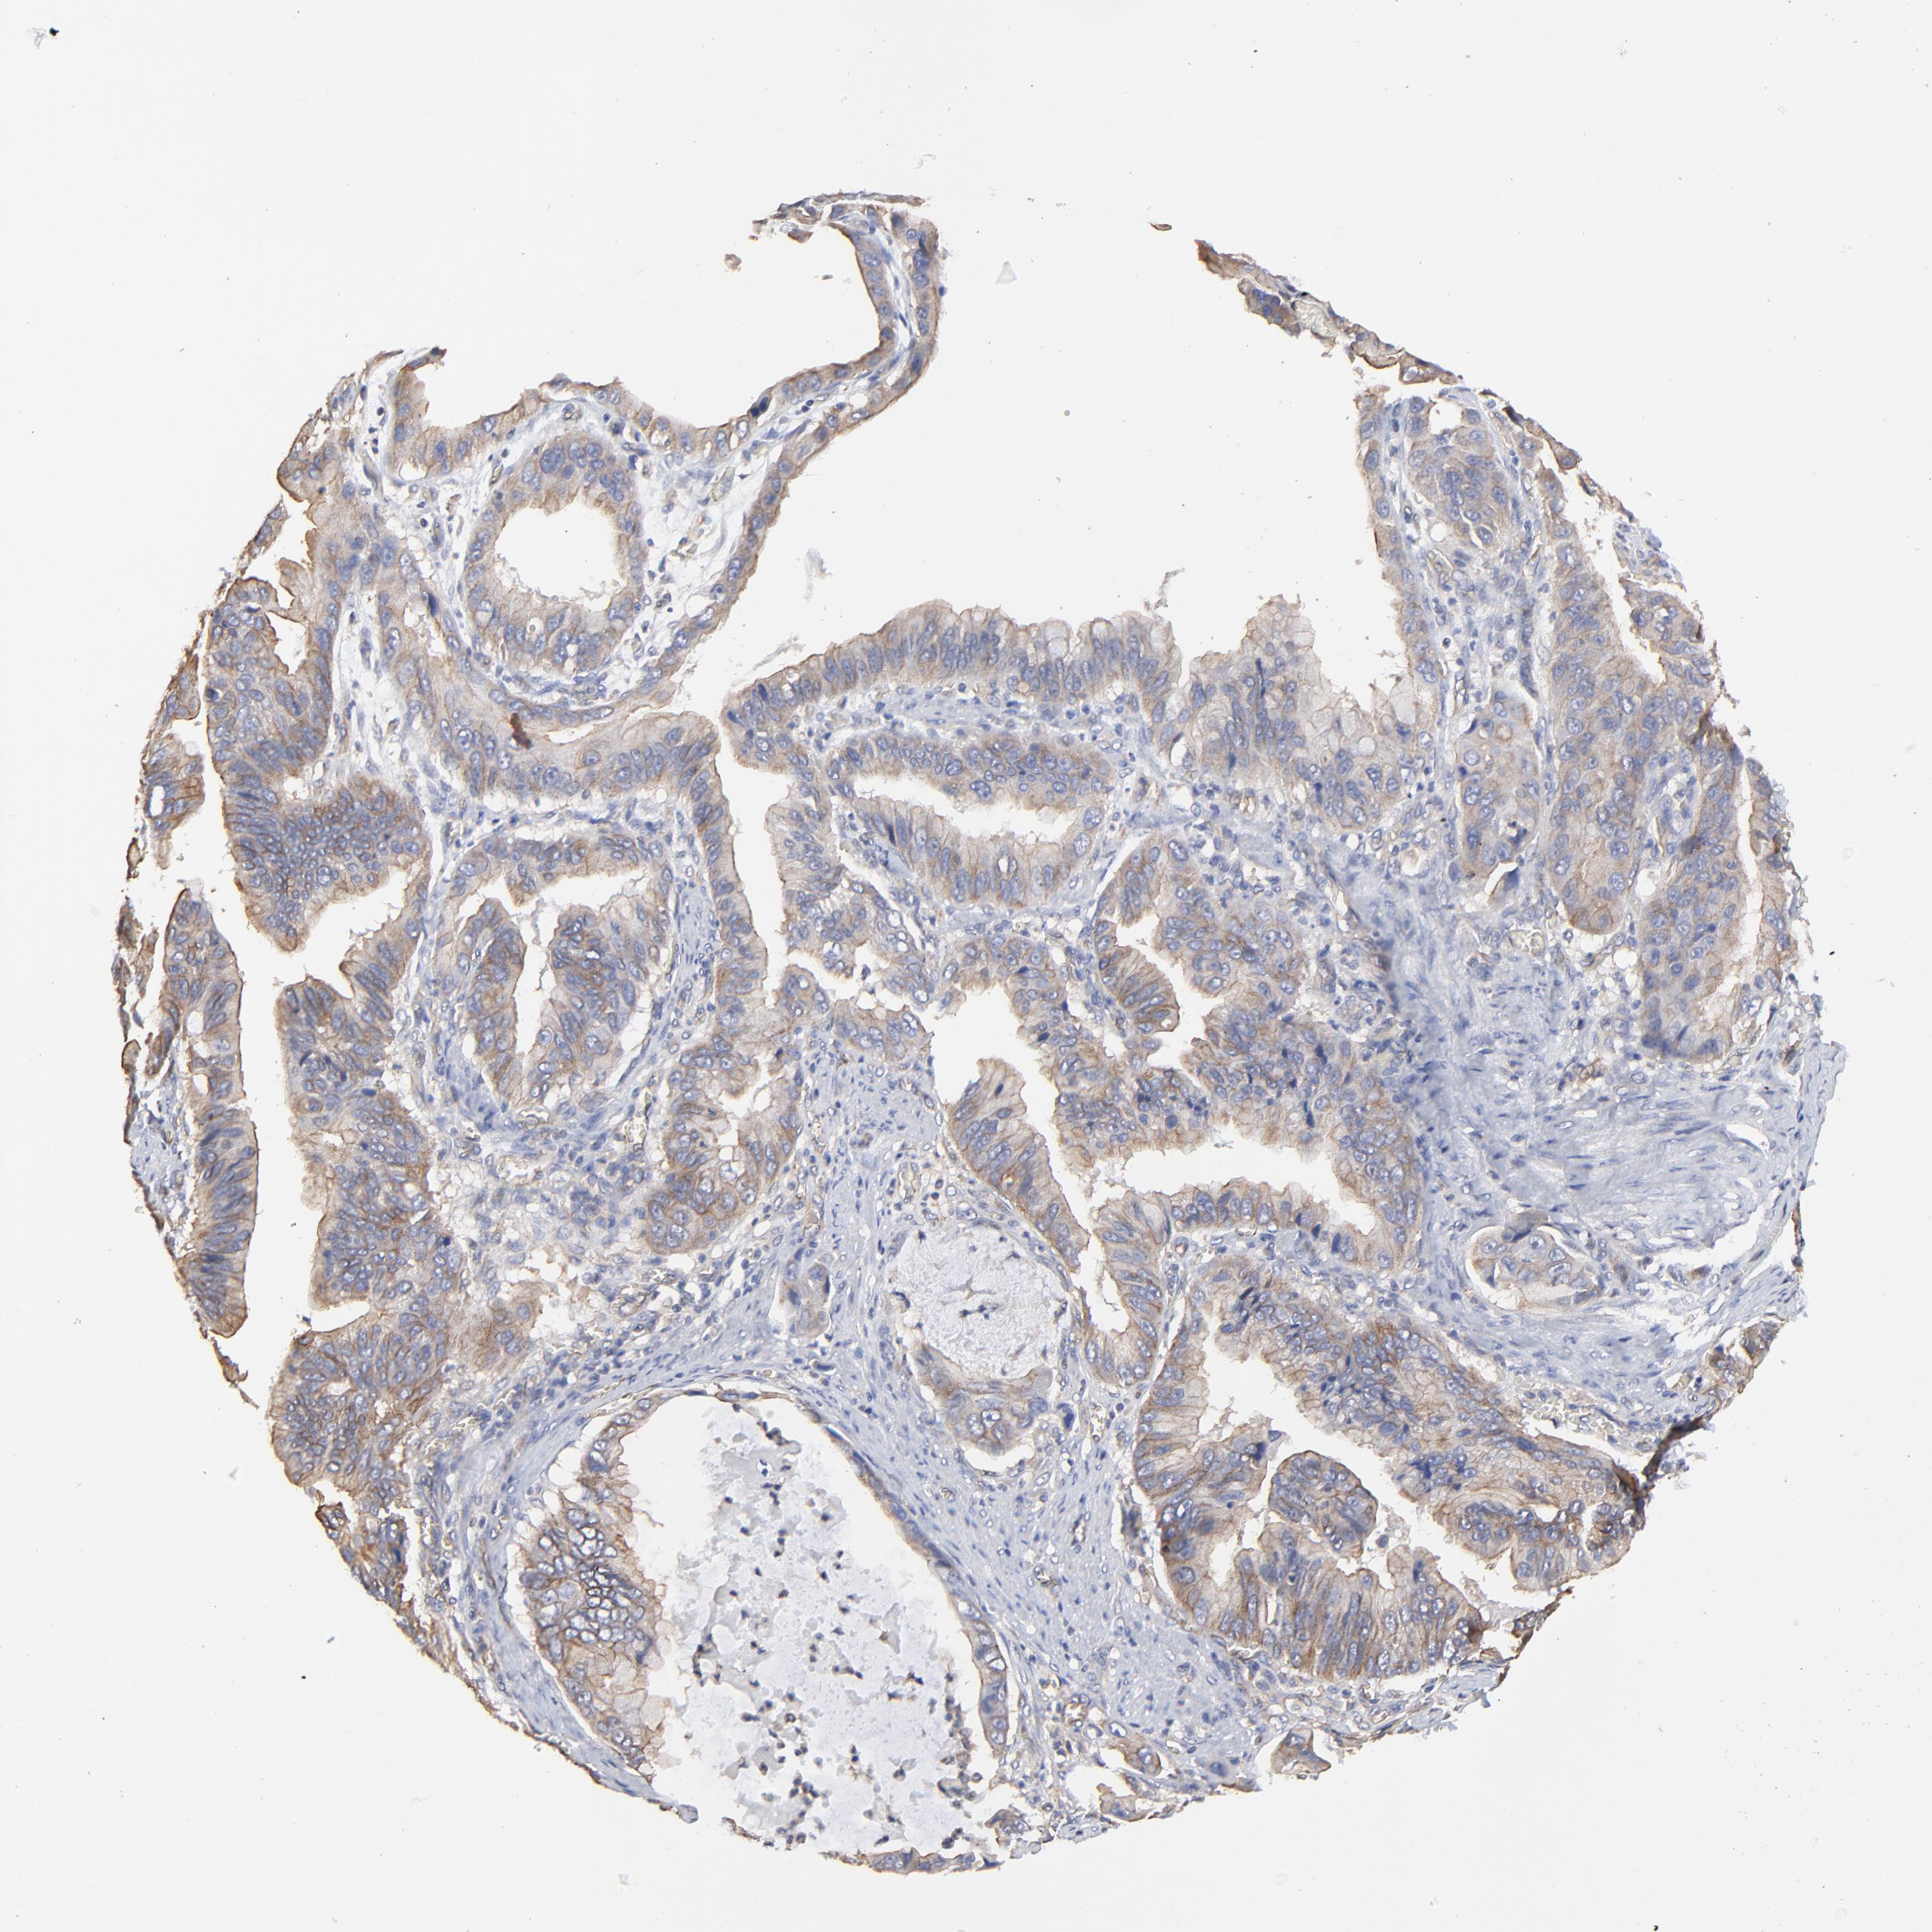

STOMACH CANCER - Protein expressioni

A mouse-over function shows sample information and annotation data. Click on an image to view it in a full screen mode. Samples can be filtered based on level of antibody staining by selecting one or several of the following categories: high, medium, low and not detected. The assay and annotation is described here.

Note that samples used for immunohistochemistry by the Human Protein Atlas do not correspond to samples in the TCGA dataset.

Antibody stainingi

Antibody staining in the annotated cell types in the current human tissue is reported as not detected, low, medium, or high, based on conventional immunohistochemistry profiling in selected tissues. This score is based on the combination of the staining intensity and fraction of stained cells.

Each image is clickable and will lead to virtual microscopy that enables deeper exploration of all samples and also displays staining intensity scores, fraction scores and subcellular localization as well as patient and tissue information for each sample.

Antibody HPA003004

Antibody HPA005819

Staining

High

Medium

Low

Not detected

Intensity

Strong

Moderate

Weak

Negative

Quantity

>75%

75%-25%

<25%

None

Location

Nuclear

Cytoplasmic/membranous

Cytoplasmic/membranous,nuclear

Adenocarcinoma, NOS